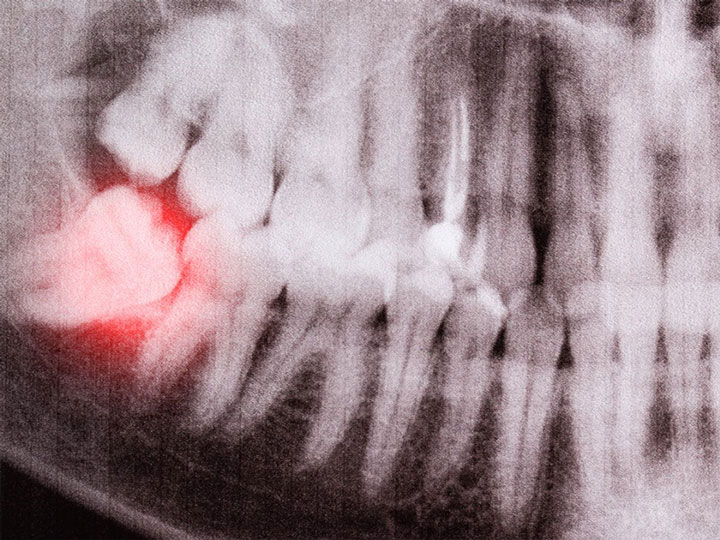

Reconocer las señales habituales que apuntan a la posible necesidad de extraer las muelas del juicio puede resultar esencial para el bienestar de tu salud bucal. Esto te permitirá tomar medidas a tiempo, evitando complicaciones y facilitando el proceso de extracción. Por lo tanto, si te sientes identificado con las siguientes señales, es aconsejable que busques una evaluación con tu dentista.

La presencia de dolor en la parte posterior de la boca podría indicar que las muelas del juicio están causando inflamación o irritación en la zona. Asimismo, si notas hinchazón alrededor de estas muelas, podría ser una señal de una posible infección o inflamación en curso. Además, es importante saber que el dolor no se limita únicamente a la boca, ya que podría irradiarse hacia la mandíbula, el oído o incluso la cabeza. Esta sensación de malestar en otras áreas puede estar relacionada con el proceso de erupción de las muelas del juicio, que puede ejercer presión en estructuras cercanas.

Finalmente, el apiñamiento dental es otro factor que podría indicar la necesidad de considerar la extracción de las muelas del juicio. Al ser unas muelas adicionales en la parte posterior de la boca a menudo tienen dificultades para encontrar suficiente espacio, lo que puede llevar a que presionen los dientes circundantes, causando desplazamiento o apiñamiento dental.